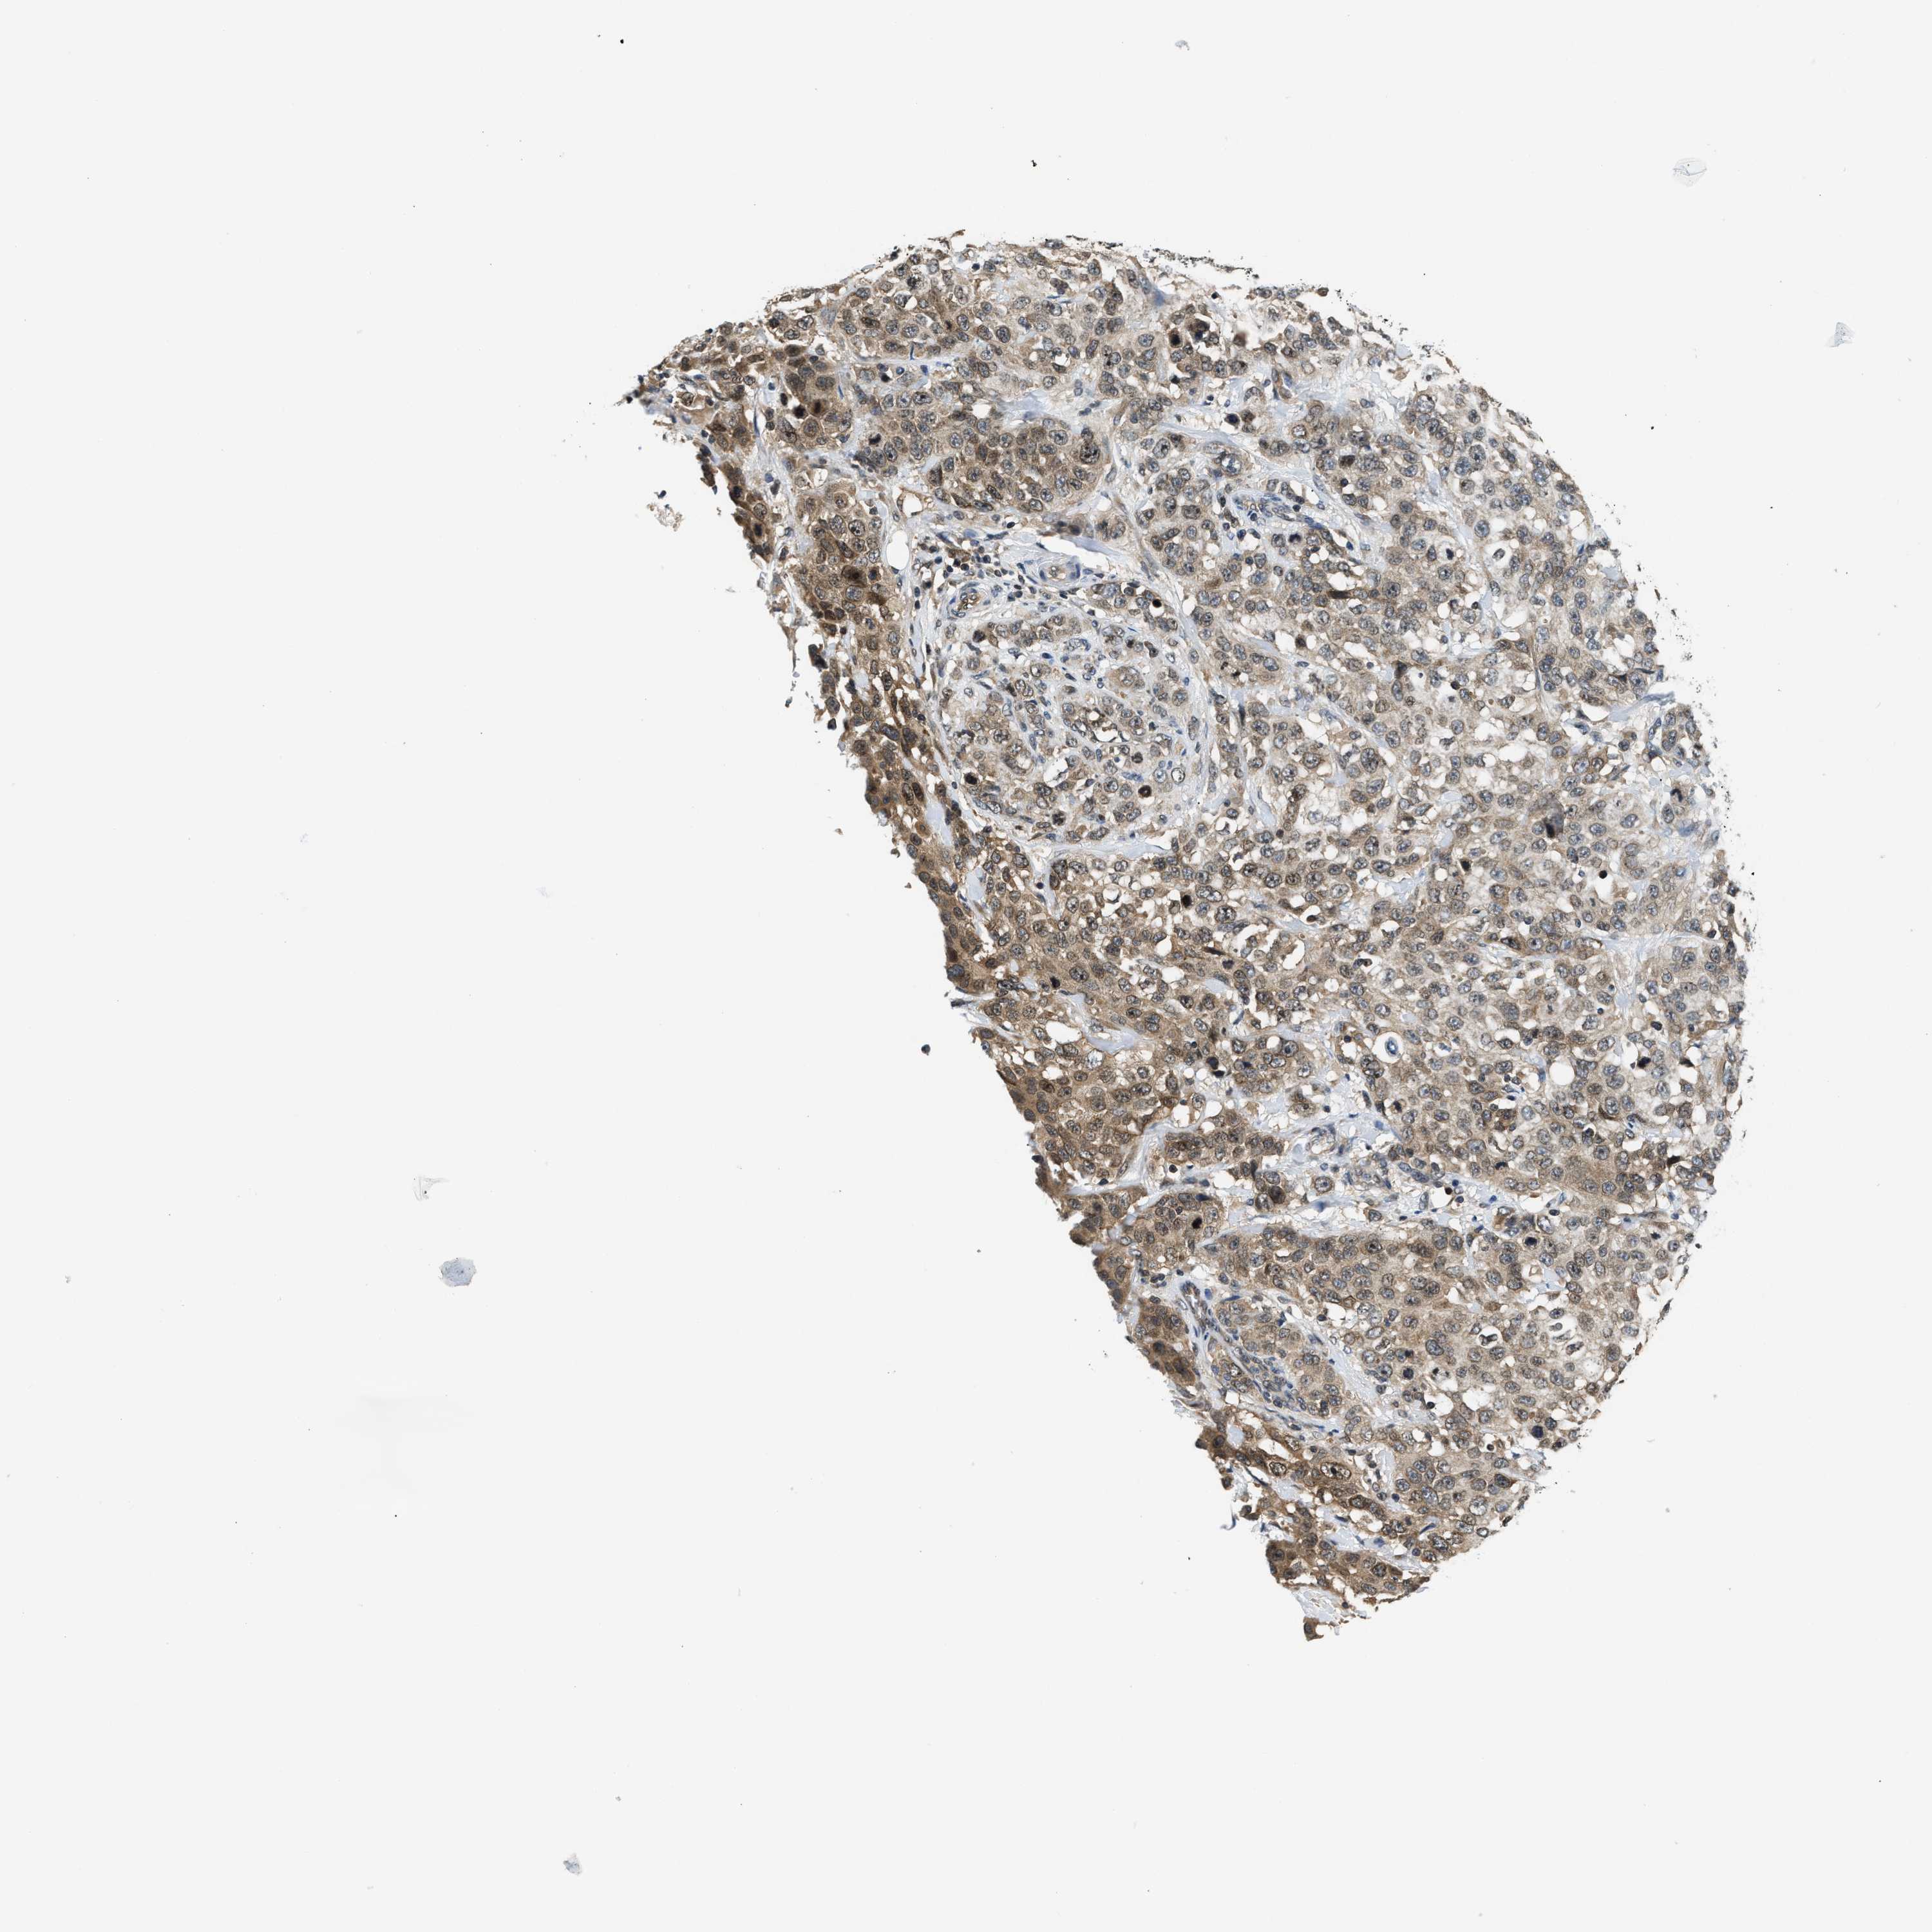

STOMACH CANCER - Protein expressioni

A mouse-over function shows sample information and annotation data. Click on an image to view it in a full screen mode. Samples can be filtered based on level of antibody staining by selecting one or several of the following categories: high, medium, low and not detected. The assay and annotation is described here.

Note that samples used for immunohistochemistry by the Human Protein Atlas do not correspond to samples in the TCGA dataset.

Antibody stainingi

Antibody staining in the annotated cell types in the current human tissue is reported as not detected, low, medium, or high, based on conventional immunohistochemistry profiling in selected tissues. This score is based on the combination of the staining intensity and fraction of stained cells.

Each image is clickable and will lead to virtual microscopy that enables deeper exploration of all samples and also displays staining intensity scores, fraction scores and subcellular localization as well as patient and tissue information for each sample.

Antibody HPA026303

Antibody CAB020822

Staining

High

Medium

Low

Not detected

Intensity

Strong

Moderate

Weak

Negative

Quantity

>75%

75%-25%

<25%

None

Location

Nuclear

Cytoplasmic/membranous

Cytoplasmic/membranous,nuclear

Adenocarcinoma, NOS

Adenocarcinoma, High grade